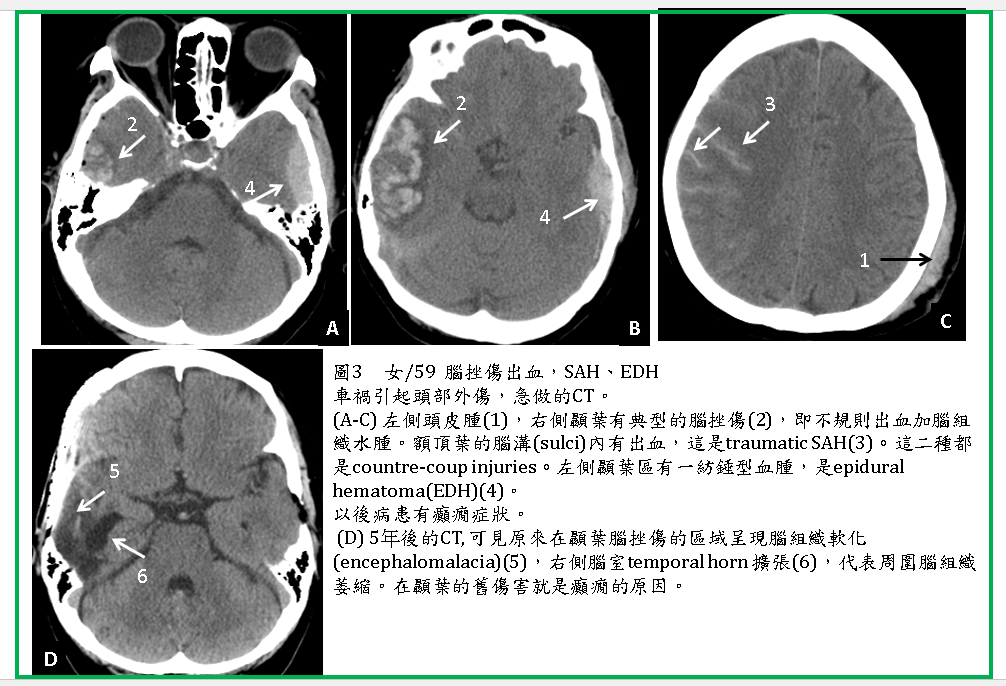

是最常見的類型,在撞擊受傷的區域有不規則的腦水腫及多個點狀,或小塊狀出血。有些只有一個區域contusion (圖3) ,有些則多處(圖1,2,4,5)。

2. 腦挫傷常常合併SDH、EDH(圖1),也常合併SAH (圖3,4,5,6)、IVH 。

腦挫傷區域時間久後血塊會逐漸吸收,會演變成腦軟化(encephalomalacia) (圖1,3),甚至囊化(cavitary change),會引發癲癇(seizure),嚴重的腦挫傷也是造成智能損害甚至植物人的重要原因。